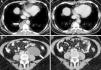

A 53-year-old woman was diagnosed with lymphangioleiomyomatosis (LAM) in 2010, presenting diffuse pulmonary involvement with multiple fine walled cysts, right retrocrural cystic lymphangioleiomyomas, and multiple retroperitoneal tumors of cystic appearance, consistent with abdominal lymphangioleiomyomas, the largest being 6.8×3.9×5.1 in diameter (Fig. 1 A and B). Lung function on diagnosis showed forced vital capacity (FVC) 3300ml (98%), forced expiratory volume in 1 second (FEV1) 2370ml (82%) and an FEV1/FVC ratio 69%. Carbon monoxide diffusing capacity (DLCO) was 89%. She reported symptoms of dyspnea on heavy exertion and intermittent episodes of predominantly catamenial chest and abdominal pain. After 2 years of follow-up, lung function had significantly worsened, with FEV1 2040ml (71%) and DLCO 72%, increased basal dyspnea, and catamenial symptoms persisted. In view of her clinical and functional progression, treatment was started with the mammalian target of rapamycin (m-TOR) inhibitor sirolimus at a dose of 2mg/day.1 One year after beginning treatment, a follow-up radiological examination showed practically complete resolution of the thoracic and abdominal lymphangioleiomyomas2 (Fig. 1C and D). Clinical improvement and stabilized lung function were observed, with FEV1 1980ml (70%) and DLCO 82%. This image shows the beneficial effect of sirolimus in reducing the size of the thoracic and abdominal lymphangioleiomyomas, and in stabilizing lung function in patients with LAM.

Chest computed axial tomography (CAT) (A) showing a right paravertebral cystic lesion 3.2×1.9cm, consistent with retrocrural lymphangioleiomyoma. Abdominal CAT (B) showing tumor 6.8×3.9×5.1cm of retroperitoneal cystic appearance, located in the left para-aortic region, extending to the pelvis, consistent with abdominal lymphangioleiomyoma. Chest-abdominal CAT one year later (C and D) showing practically complete resolution of lesions.